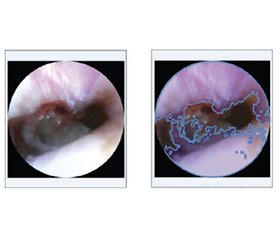

Поліпшення оцінки ушкоджень барабанної перетинки за допомогою налаштовуваного алгоритму Flood Fill

Актуальність. Точна і швидка оцінка ступеня перфорації барабанної перетинки є надзвичайно важливою в клінічній отоларингології, особливо в умовах обмежених ресурсів. Мета: розробка комп’ютерної системи із налаштовуваними інструментами сегментації, які можна швидко застосувати для поліпшення процесу оцінювання, скорочення часу, необхідного для отримання послідовних, об’єктивних і точних результатів при роботі з ендоскопічними зображеннями різної якості, контрастності, освітленості й інших змінних. Матеріали та методи. Для досягнення цієї мети розроблено спеціалізований веб-додаток із налаштовуваним адаптивним алгоритмом сегментації Flood Fill. Експерименти проводилися з використанням розробленої системи й набору ендоскопічних зображень із різними типами перфорацій, що були перевірені експертами для забезпечення якості та застосовності запропонованих моделей. Результати. Експериментальні результати продемонстрували, що адаптивний алгоритм сегментації забезпечує надійну й послідовну ідентифікацію пошкоджених ділянок, значно зменшуючи діагностичну варіативність та ймовірність неточностей. Можливість налаштування параметрів алгоритму дозволила проводити точну сегментацію навіть за неоптимальних умов зйомки (низька контрастність, розмиті зображення), вирішуючи типові клінічні проблеми. Практична корисність та інтуїтивний дизайн програми мінімізували вимоги до навчання, сприяючи потенційному швидкому клінічному впровадженню і можливості оцінювати перфорації швидше за традиційний візуальний підхід. Висновки. Запропоновані модель, метод та веб-додаток ефективно відповідають меті роботи — поліпшенню надійності діагностики й клінічного робочого процесу, заощаджуючи час спеціалістів. Розроблений інструмент має значний потенціал щодо поліпшення результатів аналізу й лікування пацієнтів в умовах надзвичайних ситуацій та обмежених ресурсів. Подальше вдосконалення за допомогою передових технологій обробки зображень може ще більше підвищити точність і застосовність в інших медичних галузях.

Background. Accurate and rapid assessment of tympanic membrane perforations is essential in clinical otolaryngology, particularly in resource-constrained environments. The purpose of the work is to develop a computer system powered by highly adjustable segmentation tools that can be quickly applied to improve the assessment, reduce the time needed for obtaining consistent, objective and precise results when dealing with endoscopic images of different quality, contrast, amount of light and other variabilities. Materials and methods. To achieve this, a specialized web-based application was developed, utilizing a modified adaptive Flood Fill segmentation algorithm. The experiments were conducted using the developed system and a dataset of endoscopic images with various types of perforations, examined by expert to ensure the quality and applicability of the proposed models. Results. Experimental results demonstrated that the adaptive segmentation algorithm provided reliable and consistent identification of damaged areas, significantly reducing diagnostic variability and probable inaccuracies. Adjustability of algorithm parameters allowed accurate segmentation even under suboptimal imaging conditions (low contrast, blurred images), addressing typical clinical challenges. The practical usability and intuitive design of the application minimized training requirements, facilitating potential rapid clinical deployment and ability to assess perforations quicker than with traditional visual approach. Conclusions. The proposed model, method and web-based application effectively meet the goal of the work — improving diagnostic reliability and the clinical workflow, saving clinicians’ time. The developed tool has substantial potential to enhance patient outcomes in emergency and resource-limited settings. Further improvement through advanced image processing techniques could increase accuracy and applicability even more broadly across other medical domains.